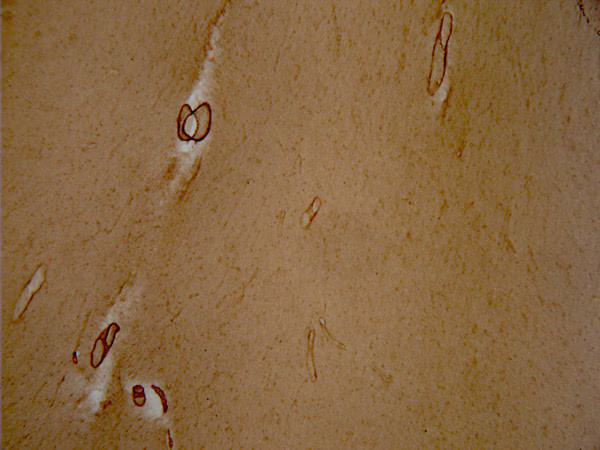

Anti-vascular Amyloid 1-42抗体[mOC31] - Conformation-Specific

描述 兔单克隆抗体[mOC31] to vascular Amyloid 1-42 - Conformation-Specific

经测试应用 适用于: Dot blot, IHC-P, IHC-FrFl

种属反应性 与反应: Mouse, Human

阳性对照 beta Amyloid (Aß) 1-42 IHC-P: FFPE human brain Alzheimer

IHC-P 1/250 - 1/500. Do not perform antigen retrieval.